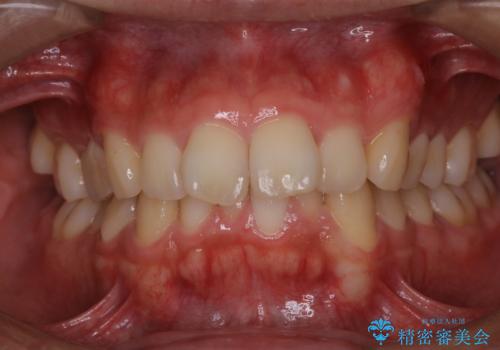

虫歯ではなく、歯の着色

- 歯が黒くて虫歯かもしれないとのことで来院されました。虫歯ではなく、着色が付着してしまっていたためPMTC30分コースできれいに除去しました。

黒や茶色くなっている部分が、着色なのか、虫歯によるものなのかは判別が難しいことがあります。そのため、定期的にPMTCを行うことで状態の確認が的確に行えます。

PMTCとは、専門的な機械や材料を使用したしっかりとしたクリーニングです。